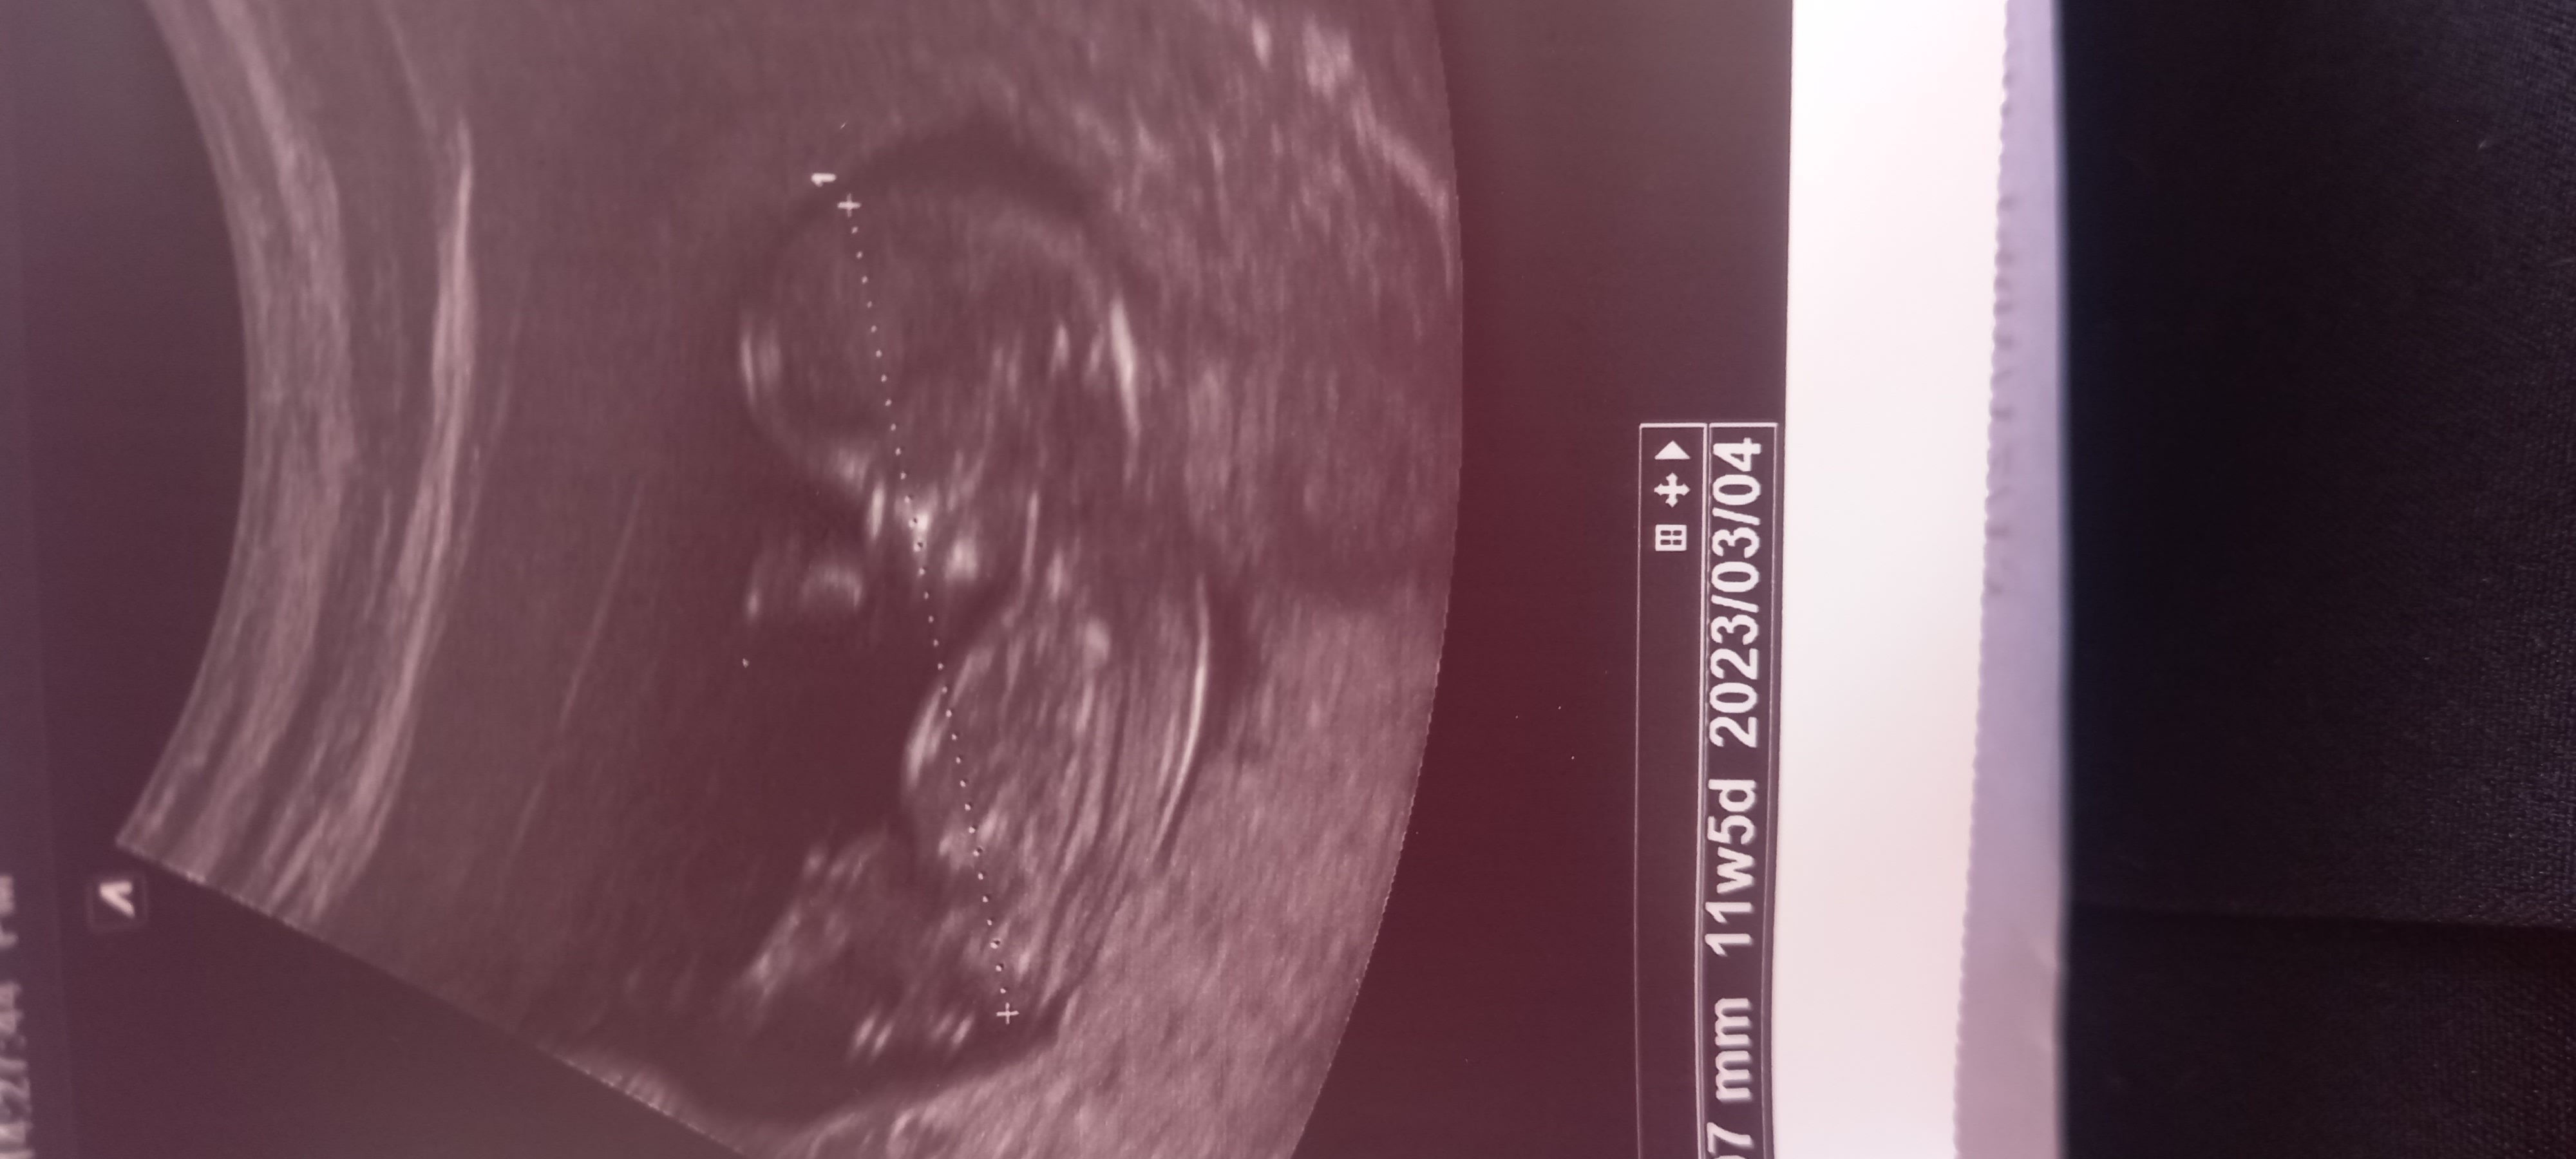

سونوگرافی ان تی وتعیین جنسیت

سلام دوستان من رفتم سونو ntاحتمال داد دختره ولی گفت چون زیر ۱۲هفته هستی امکان اشتباه هست حالا چیکار کنم چقدر امکان داره اشتباه باشه کسی بوده تا حالا

میخوام برم وسیله بگیرم یهو اشتباه در بیاد چی؟؟؟؟

اینکه به عنوان مادر ذوق داری واسه فسقلیت خرید کنی حق داری ولی یه مقدار صبر کن تا قطعی بهت بگن بعدش برو با عشق خرید کن.ان شاالله به سلامتی  و دل خوش

بله امکان اشتباهش زیاااده

منم ۱۲ هفته و پنج روز رفتم و گفت احتمالا دختره

ولی بعدا تو آنومالی که نزدیک ۱۸ هفته رفتم گفتن پسره